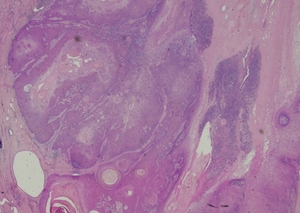

Complete excision of the horn was done with V-Y plasty, and the tissue was sent for pathological examination. A coiled horn measuring 26 cm with an attached skin ellipse measuring 4.5 x 3 cm was received in the pathology laboratory. Histopathological examination revealed a well-differentiated squamous cell carcinoma with keratin horn formation (Figs. 3 and 4). The tumour involves the upper dermis only with no vascular or perineural invasion. The lesion was completely excised with clear excision and deep margins measuring > 4mm. The patient’s surgical excision site healed well (Fig. 5), and there were no clinical recurrences over the 5-year period (the patient was seen at 3, 4, and 5 years after excision).